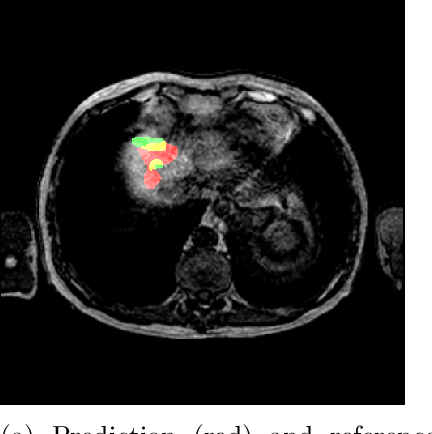

Abstract:Deep learning techniques show success in detecting objects in medical images, but still suffer from false-positive predictions that may hinder accurate diagnosis. The estimated uncertainty of the neural network output has been used to flag incorrect predictions. We study the role played by features computed from neural network uncertainty estimates and shape-based features computed from binary predictions in reducing false positives in liver lesion detection by developing a classification-based post-processing step for different uncertainty estimation methods. We demonstrate an improvement in the lesion detection performance of the neural network (with respect to F1-score) for all uncertainty estimation methods on two datasets, comprising abdominal MR and CT images respectively. We show that features computed from neural network uncertainty estimates tend not to contribute much toward reducing false positives. Our results show that factors like class imbalance (true over false positive ratio) and shape-based features extracted from uncertainty maps play an important role in distinguishing false positive from true positive predictions

Abstract:Despite the successes of deep learning techniques at detecting objects in medical images, false positive detections occur which may hinder an accurate diagnosis. We propose a technique to reduce false positive detections made by a neural network using an SVM classifier trained with features derived from the uncertainty map of the neural network prediction. We demonstrate the effectiveness of this method for the detection of liver lesions on a dataset of abdominal MR images. We find that the use of a dropout rate of 0.5 produces the least number of false positives in the neural network predictions and the trained classifier filters out approximately 90% of these false positives detections in the test-set.